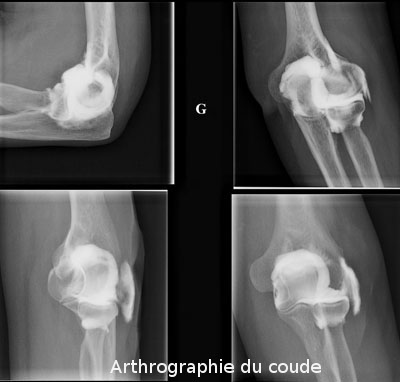

L'arthrographie est un examen radiologique consistant à introduire un produit de contraste en intra-articulaire (apparaissant en blanc sur les clichés) afin de démontrer l'intégrité ou la présence de lésions de structures intra-articulaires comme les cartilages, les ligaments, etc.

L'arthrographie est donc une technique qui utilise les rayons X et des agents de contraste qui sont en principe à base d'iode. Les articulations les plus fréquemment examinés sont l'épaule,le genou, le poignet, la hanche et la cheville.

coude (présence de corps intra-articulaires, évaluation du cartilage)